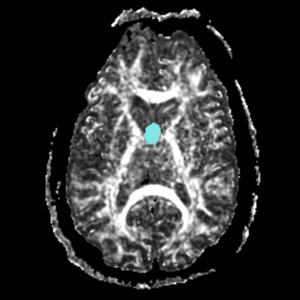

ROI 1 was drawn on the sagittal slice, 5 slices superior to the anterior commisure (Fig. 8 & 10). ROI 2 was drawn on a coronal slice where the crux of the fornix was present. It was not always the same slice for both sides (Fig. 9 & 11).

Figure 8. Axial View of ROI 1

Figure 9. Coronal View of ROI 2 (left=11, right=13)

The color coding of the resulting ROIs is as follows:

ROI 1: Left & Right (7)

ROI 2: Left(8) - Right(6)